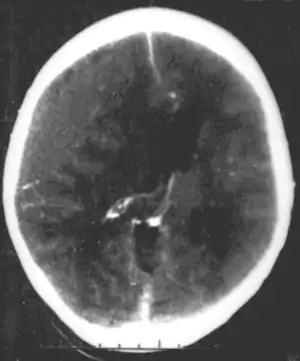

Systemic infections can result in neurodevelopmental consequences, when they occur in infancy and childhood of humans, but would not be called a primary neurodevelopmental disorder. For example HIV[26] Infections of the head and brain, like brain abscesses, meningitis or encephalitis have a high risk of causing neurodevelopmental problems and eventually a disorder. For example, measles can progress to subacute sclerosing panencephalitis.

A number of infectious diseases can be transmitted congenitally (either before or at birth), and can cause serious neurodevelopmental problems, as for example the viruses HSV, CMV, rubella (congenital rubella syndrome), Zika virus, or bacteria like Treponema pallidum in congenital syphilis, which may progress to neurosyphilis if it remains untreated. Protozoa like Plasmodium[26] or Toxoplasma which can cause congenital toxoplasmosis with multiple cysts in the brain and other organs, leading to a variety of neurological deficits.

Brain trauma in the developing human is a common cause (over 400,000 injuries per year in the US alone, without clear information as to how many produce developmental sequellae)[39] of neurodevelopmental syndromes. It may be subdivided into two major categories, congenital injury (including injury resulting from otherwise uncomplicated premature birth)[6] and injury occurring in infancy or childhood. Common causes of congenital injury are asphyxia (obstruction of the trachea), hypoxia (lack of oxygen to the brain) and the mechanical trauma of the birth process itself.